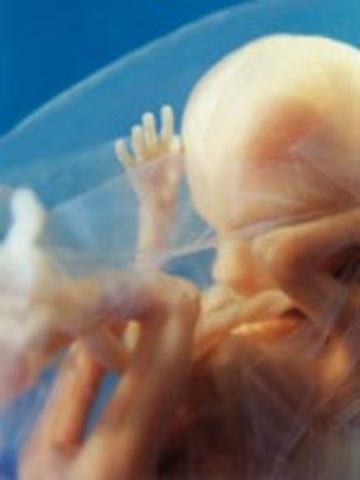

• Week 9: Fingers and Toes Form

Week 9: Fingers and Toes Form

Many more body parts are forming such as the tongue, the bones, eyelids, etc. The fingers and toes are the most defined. The baby is developing in a little bag of fluid which it is swimming around in.

• Week 10: Embryo is Now a Fetus

Week 10: Embryo is Now a Fetus

The embryo is now called a fetus until birth. The fetus is the size of a small strawberry. The fingerprints are becoming evident in the skin and the nipples and hair follicles are forming as well.